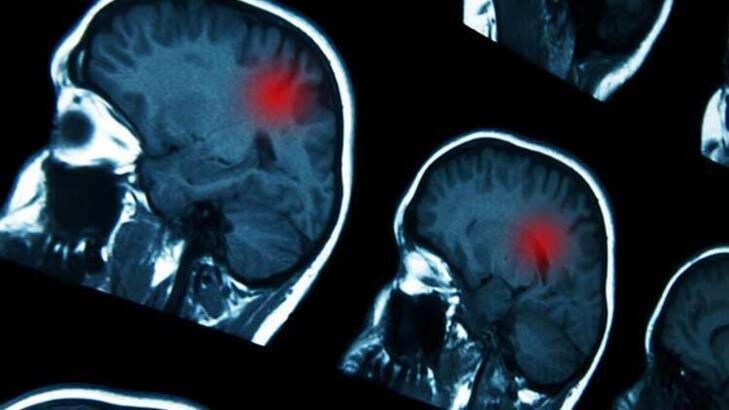

Radyoloji Kliniği'nden Uzm. Dr. Mustafa Demir de inmede ilk 4-6 saatin başarılı bir tedavi açısından kritik olduğuna işaret ederek, “Bu süreyi bazen 8 saate de uzatabiliyoruz ama süre ne kadar uzarsa, hastanın tedaviden fayda görme ihtimali o kadar düşüyor" dedi. Dr. Demir, İnanır'ın evde şikayetleri başladıktan yaklaşık 1 saat sonra 112'ye haber verilmesiyle hastaneye getirildiğini ve ambulansla hastanede tetkiklerinin yapılıp girişimsel radyoloji ekibinin tedaviye başlamasının yaklaşık 20 dakika sürdüğünü, evde şikayetlerinin başlamasından itibaren toplamda 1,5-2 saat sonra tedavisinin tamamlandığını vurgulayarak şu bilgileri verdi:

İlk 6 saat bizim için çok değerli. Bu 6 saatin de özellikle ilk 3 saati. Çünkü ne kadar erken müdahale edersek o kadar fazla dokuyu yeniden kanlandırıp kurtarabilme şansımız oluyor. Zaman geçtikçe hem bu kurtarma işlemi bu kadar garantili bir şekilde ortaya çıkmayabiliyor hem de gecikmeden kaynaklı birtakım komplikasyonları daha sık görebiliyoruz. İnmeye akut dönemde müdahalenin yapılabilmesi için hastanın böyle bir merkeze götürülmesi çok önemli. Bunun için de mutlaka 112'den destek almak gerekiyor. Kendi başımıza çıktığımızda, hangi hastanede inme merkezi olup olmadığını bilemeyebiliriz. Ancak 112 merkezleri hastanelerin acilleriyle daha hasta yoldayken iletişime geçtiği için zaman kaybı önleniyor."